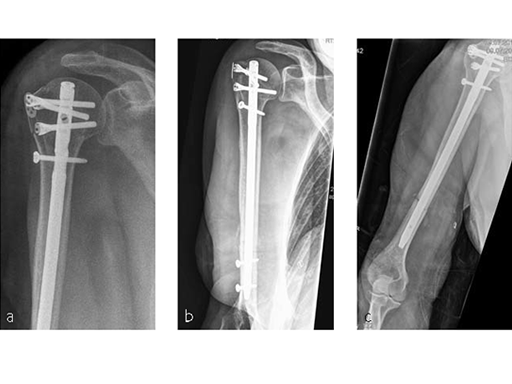

Following a fall downstairs, a 70-year-old woman sustained a head injury with intracerebral and subdural haematoma, as well as a complex fracture of the right humerus, representing a minimal displaced proximal and an oblique fracture in the distal part of the humerus (Fig 11).

After neurosurgical intervention, surgery of the humerus was planned 10 days after the index trauma. The patient was still at the neurological intensive care unit and a preoperative clinical examination of the patient, regarding radial nerve palsy, was not possible. Therefore, a surgical revision with exploration of the radial nerve and an osteosythesis of the humerus using a long MultiLoc Humeral Nail was indicated.

The patient was operated on in beach chair position. For the exploration of the radial nerve, a limited anterolateral approach was used. The nerve was mobilized and retracted laterally. An anterolateral approach to the proximal humerus was performed. The supraspinatus showed a small acute rupture without retraction. The supraspinatus tendon was split to get access to the insertion area on the humeral head. A 270 mm long MultiLoc Humeral Nail of 8.5 mm diameter was inserted under visual and x-ray control to the desired endpoint. Reduction of both the proximal and the distal humerus fracture was anatomical. In the lateral view there was a small gap, and it was decided to apply compression after distal locking (Fig 12). Proximally, three MultiLoc screws were inserted and a 2 mm end cap was placed. Finally, the supraspinatus rupture was reconstructed with transosseous sutures and secured with an augmentation plate. The posterior greater tuberosity fracture was secured with Fiber Wire to the MultiLoc screws. Fig 13 illustrates the definitive fixation.

Postoperatively, no sling was used because the patient stayed in medically induced coma.